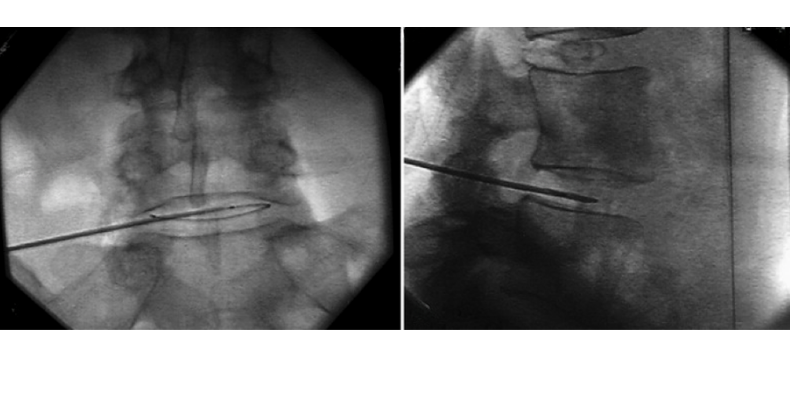

Transforaminal epidural enjeksiyon (TFESE), omurga sinir köklerinin çıktığı foramen adı verilen açıklıktan, inflamasyonu azaltmak amacıyla anestetik ve steroid karışımı enjeksiyon yapılmasıdır. Bu işlem, sinire doğrudan etki ederek ağrının kaynağını hedef alır. Floroskopik (X‑ray) rehberlik ile yüksek hassasiyetle uygulanır; iğne, direkt sinir kökü yakınlarına yönlendirilir

Seri çalışmalara göre transforaminal yaklaşım, sinir kökü yakınlığı sayesinde interlaminar veya kaudal yaklaşım kadar etkili bulunmakta; özellikle ilk iki hafta içinde daha hızlı rahatlama sağlar.